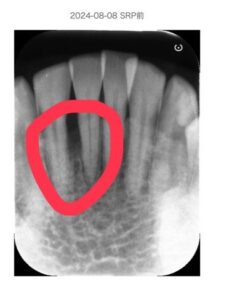

【症例例】咬合管理で安定したケース

50代 性別 男性

前歯に6mmの歯周ポケットと動揺あり。

歯周基本治療と咬合調整後

再生療法併用。

3ヶ月後にはポケットは3〜4mmに改善し、現在も安定しています。

Before:

北新地での歯周病治療前の口腔内写真|歯ぐきの腫れと炎症が見られる状態